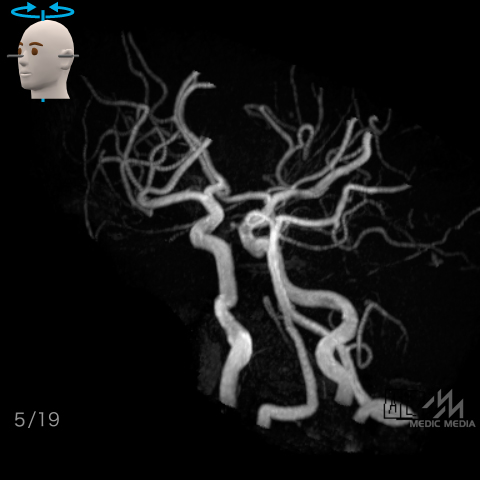

脳動脈(MRA像)

スライド(画像下)を動かし脳動脈の解剖を確認しましょう.

左右軸回転

動脈名表示

動脈名表示+色分け